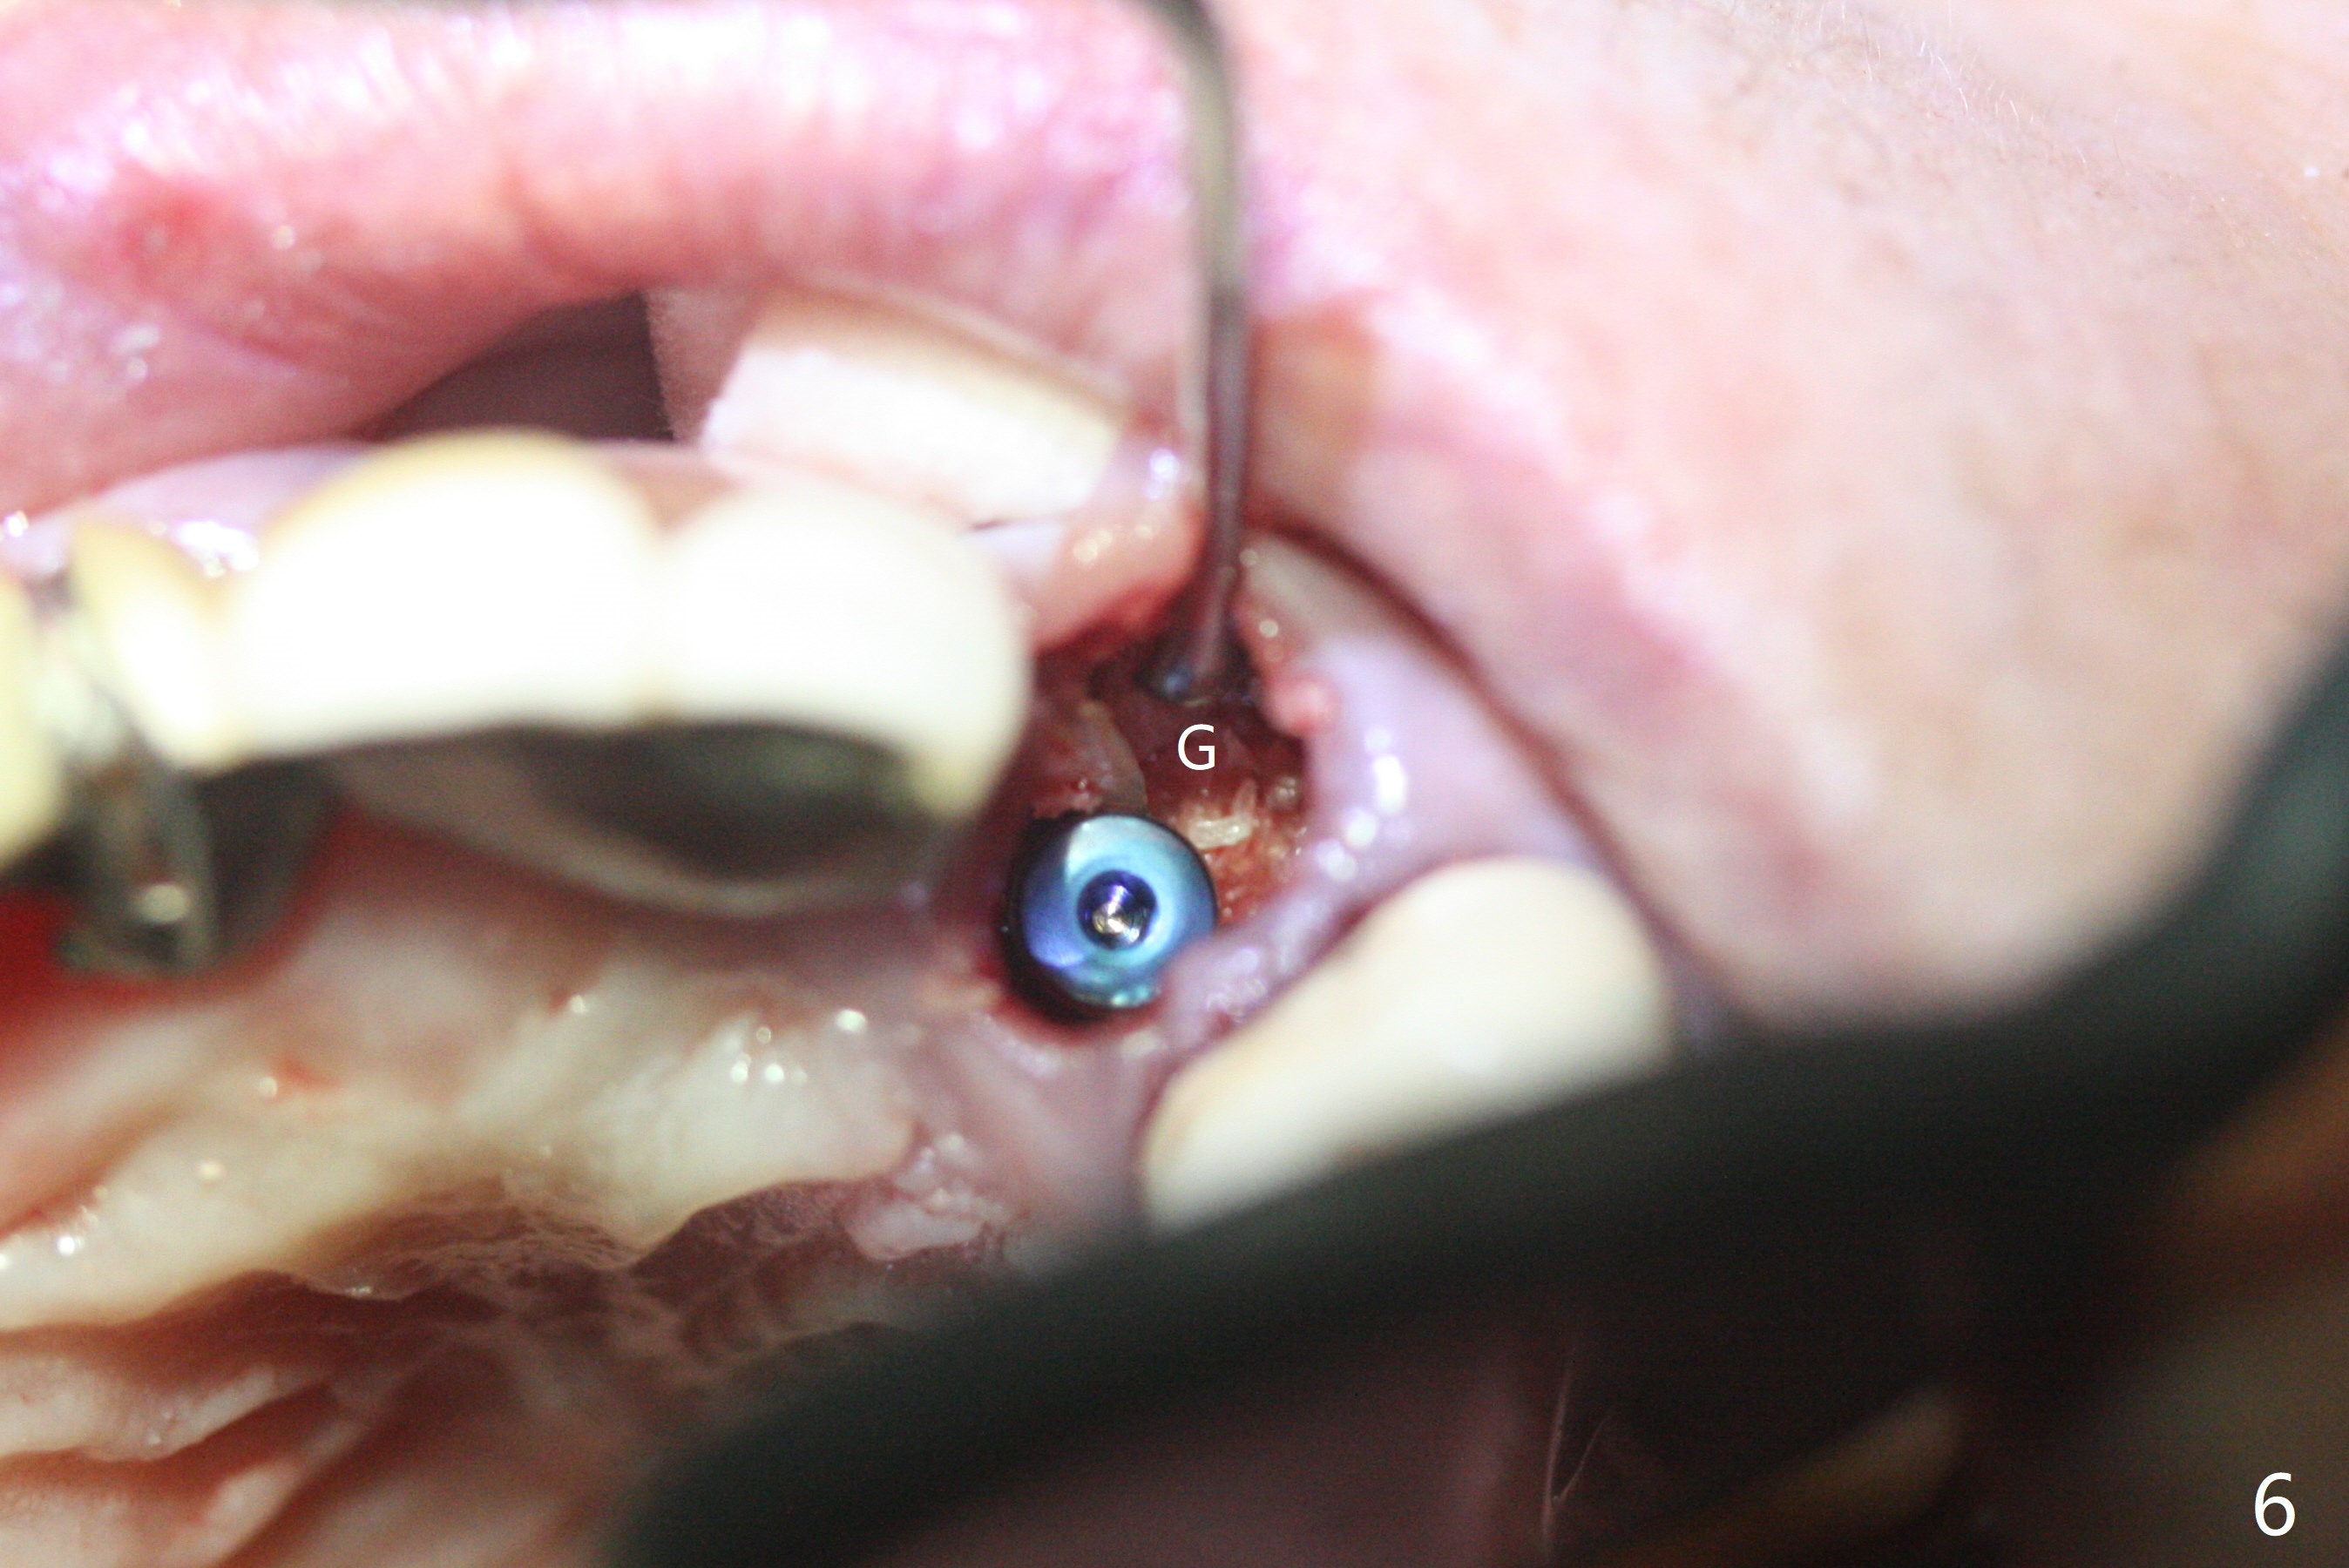

上前牙桥撤除显示右上1,2牙齿以及左上2叶片状植体好像可以保留,而左上3牙齿不能(图一,二(<:托牙边缘压迹)),拔除左上3牙齿后, 暂时把牙桥回位(图三:FPD(已经去除左上3号牙牙冠))作为3号牙种植位置参考(图四至六(G:骨粉))。其实植入前,当最后一个钻头还在原位,将PRF膜和粘性骨放置颊侧根尖(但愿骨粉能放深点),因为那里骨质很薄,好像缺损。由于植体扭力很低(大约5Ncm),放置骨粉覆盖植体(图七),为了不用缝线,涂牙周胶水(图八),放置胶原膜(图九),再涂胶水(图十)固定,最后利用右上1,2号牙(去龋,build-up后)和左上2植体制作临时牙桥,并且覆盖左上3牙槽窝。术后即刻CT显示植体颊侧(B)骨粉(图十一:*)。<:植体根尖仍有间隙,植体应该再长2毫米,初步稳定性会好些。左上3植牙愈合后,将与左上2植体制作左上1-3悬臂桥,右上1,2号牙将做根管治疗,桩,牙冠。临时牙桥术后十一天松动,右上一,二牙牙髓活性测定正常,深洗后,再次build up,不小心把左上3胶原膜吹掉,下面骨粉还稳定。术后三周病人回来做右上六种植,前牙临时修复体(图十二)需要修改(图十三)。拍摄三个方向照片显示前牙牙龈乳头(颊侧和咬合面)。